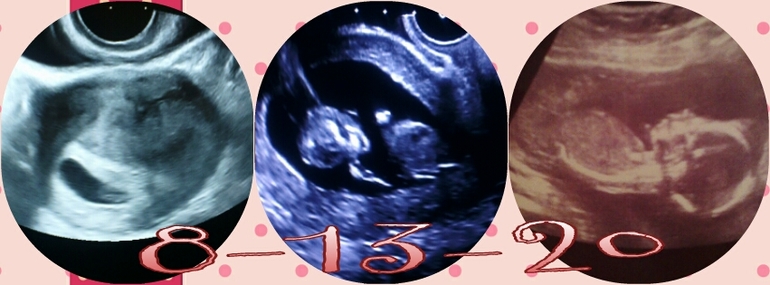

Второе скрининговое узи!!!:)

Ура Ура!!! Наконец-то вчера мы с мужем сходили на узи...вместе! Для меня это было очень и очень важно)) И к тому, врачу, кот.мне нравится и как профессионал и как человек))

Малыш активно двигается)) Слава Богу! Несмотря, на то, что пиночки я начала чувствовать, но пока не уверенные и бывали разные сомнения)) Но нет, активничает да еще как)) Посмотрели как зевает, двигает ручками и ножками...это непередаваемо)) Для мужа это было что то из области фантастики, сидел раскрыв рот и постоянно спрашивал, а пол? на что врач, каждый раз отвечала, я пока измерения делаю и улыбалась на нетерпеливых будущих родителей)))

Врач спросила, кого хотели бы и кто по нашим ощущения, мы говорим, мальчик почему то кажется, она мол мамочки редко ошибаются, но похоже на ДЕВОЧКУ!!!!!!!!!!! О-о-о, это настолько неожиданно и непривычно, правда недели за две в голову начали закрадываться мысли о платишках да бантиках, но я отмахивалась, думала неее, не мое))) Мы рады с мужем, так приятно обращаться к ребенку не в среднем числе, а называть доченька))) Тонусов и отклонений нет, все хорошо) Голова нашей девчушки чуть выше пупка и ребенок преимущественно слева, как я и ощущала, но сомневалась) Значок меняю на розовый, в надежде что ничего уже не изменится)))